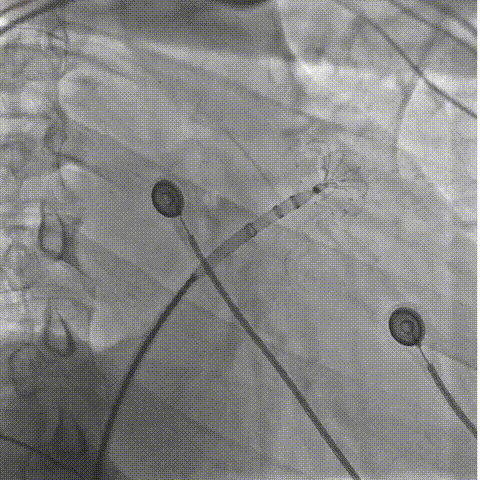

牵拉实验

打开封堵伞造影